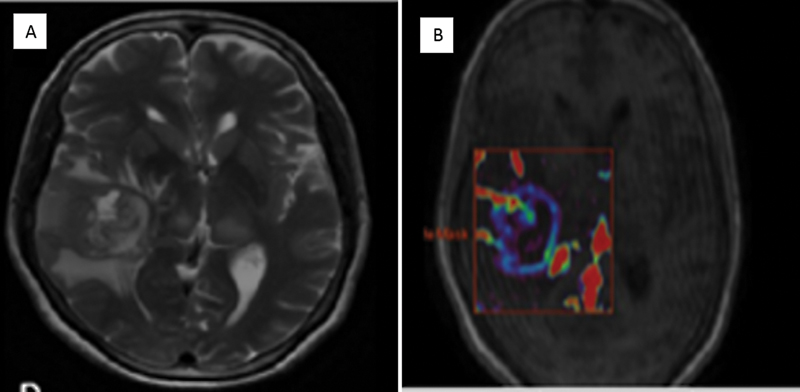

| Figure 2:Case of diffuse large B cell lymphoma. T2-weighted imaging reveals a small area of hyperintensity in the genu of the corpus callosum. (A). Percentage signal recovery is high (red curve) on dynamic susceptibility contrast perfusion imaging in lymphoma with mild elevation in relative cerebral blood volume (B).